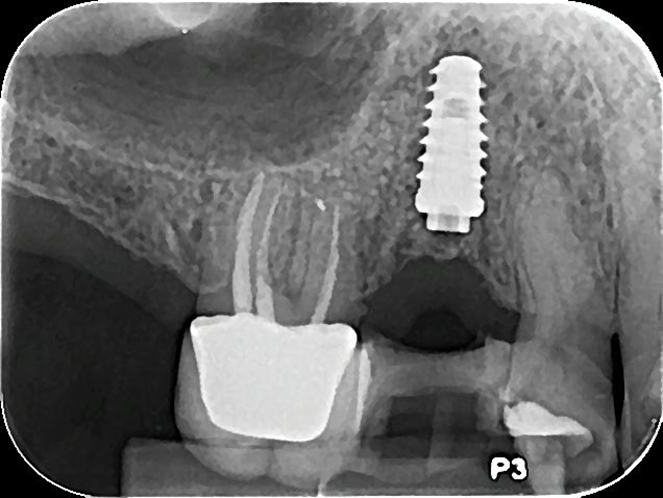

No presente caso, o paciente procurou nossa clínica acreditando que a coroa sobre implante do 15 estava apenas frouxa, e que seria possível resolver apertando o parafuso. Ao exame clínico, apresentava uma coroa cimentada sobre componente UCLA fundida e parafusada diretamente sobre o hexágono do implante (um HE de 3.5 mm de diâmetro e plataforma da mesma medida). Após o corte da coroa para acessar o parafuso, na remoção do conjunto, a plataforma do implante veio anexada à coroa, denotando a fratura do implante, que foi comprovada com radiografia periapical (Figuras 1 e 2). Decidimos por fazer uma prótese adesiva provisória (Figuras 3 e 4) e planejar a remoção do implante com colocação imediata de novo implante, após observado na tomografia cone beam que haveria osso suficiente para isso (Figura 5). O implante foi removido (Figuras 6 e 7) com o uso de broca trefina e fórceps, e um implante Implacil De Bortoli CM Due Cone foi instalado no mesmo momento (Figura 8), com regeneração óssea guiada (ROG) na parede vestibular (Figura 9), que havia ficado muito fina (enxerto ósseo particulado + membrana de colágeno). Apesar de termos obtido bom travamento do implante (45 Ncm), optamos por deixá-lo sem carga pelo período de cinco meses, para respeitar o tempo da ROG (Figuras 10 e 11).